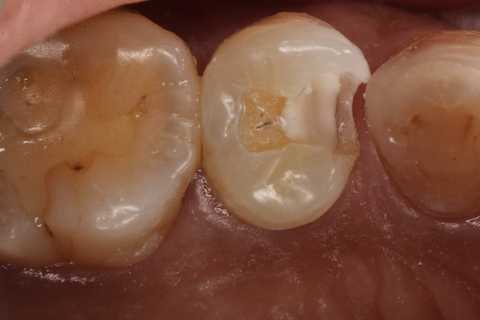

40代女性、左上5、冷水痛+

注意点はCRの接着面は新鮮歯質を確保して歯髄に近いところの軟化象牙質はあまり追求しないでも良い。α-TCPセメントの硬化と接着を妨げない程度に乾燥できれば良い。軟化象牙質は原材料のα-TCPと多少の水分があれば自然に再硬化するようだ。

この症例はストリップスを使っていない。使わない方が確実に充填できると思う。

では時系列でどうぞ